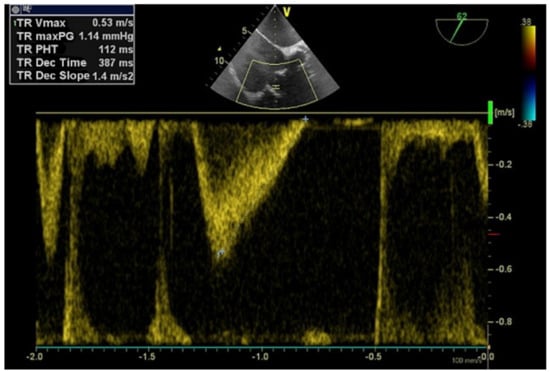

The delivery system, the introducer sheath and the guide wire were removed after confirming the position and the competence of the TTVIV by TEE (Figure 5). After extracting all materials, the two purse strings were ligatured followed by meticulous hemostasis. The right lung was reinflated using the Valsalva maneuver and a drainage catheter was inserted in the right costodiaphragmatic recess before closing the thoracotomy site. Postoperative evolution was uneventful, and the patient was discharged after two weeks with NYHA class II heart failure compared to IV at admission.

Figure 5. Transoesophageal echocardiography mid-oesophageal four-chamber incidence confirming the normal functioning the tricuspid bioprosthetic valve-in-valve with a maximum transvalvular gradient of 1.14 mmHg and a peak velocity of 0.53 m/s, suggesting substantial reduction in gradient severity after transcatheter valve implantation.